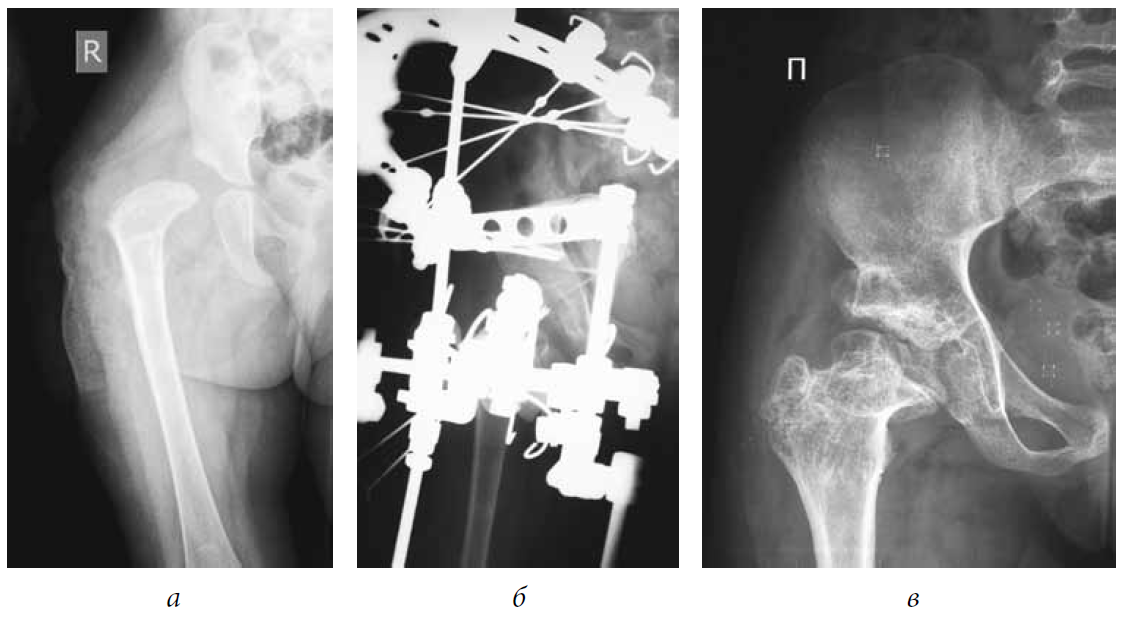

There were no cases among the joints examined that presented with an excellent outcome. Good results were noted only when performing extra-articular interventions (see Table 2). In general, positive outcomes were observed in 94% (Figs. 1–3).

Fig. 1. Patient M., 5 years old, with a diagnosis of subluxation of the left hip, degree II of dislocation, and degree IV Perthes disease: a — frontal radiograph of the hip joint before treatment; b — frontal radiograph of the hip joint during treatment (after tunneling of the femoral neck and head, extra-articular reconstruction of the pelvic and femoral components of the joint, hardware decompression of the joint); c — frontal radiograph of the hip joint 5 years after treatment